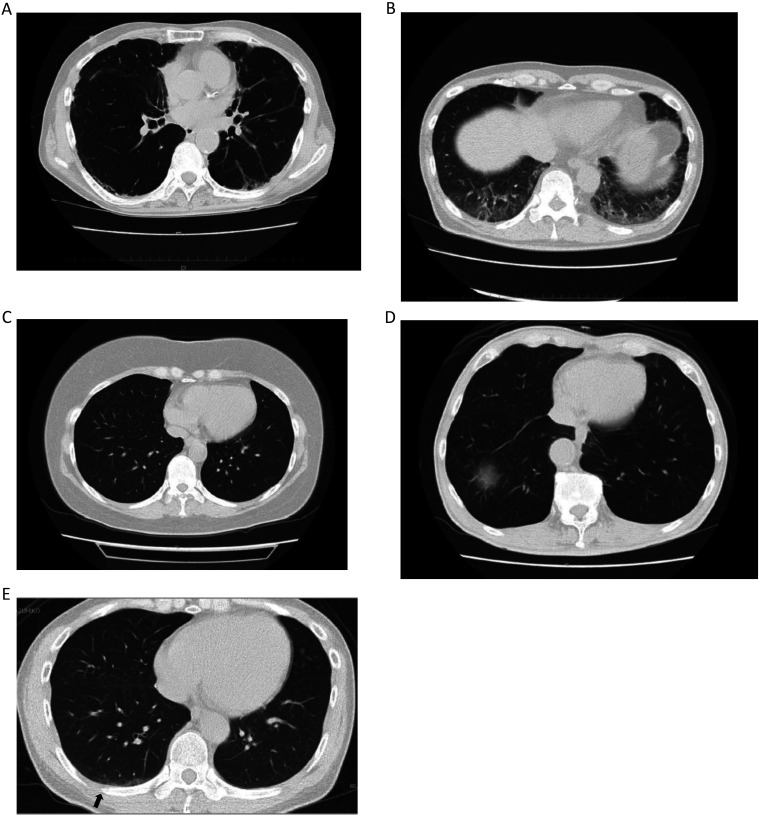

In 2002, Daikin Industries' Yodogawa Plant (DIYP) in Settsu City in Japan had contaminated drinking water in Hanshin area with (PFOA), leading to the complete cessation of PFOA production in 2012. In 2023, local residents conducted a voluntary Blood Monitoring Campaign with 1,182 general residents. Blood monitoring was also conducted for former or current workers from DIYP and farming residents in Settsu City. Serum PFOA concentrations determined by gas chromatography with mass spectrometry [number: ng/ml: median (25th-75th percentile)] were as follows: former and current workers [N=7: 192.6 (23.3-596.6)] >farming residents [N=5: 70.2 (50.4-98.8)] >general residents [N=1182: 5.0 (3.3-7.0)] with significant differences (Kruskal-Wallis test, p<0.001). In a study, 4 out of 5 farming residents showed a serum PFOA decline (half-life: 2.2 yr, 95% CI: 1.4-4.6) after stopping local agricultural product consumption. However, 3 former workers exhibited no decrease over 0.8-0.9 yr. An investigation found that 5 of the 7 subjects were likely exposed to dust from the polymerization of tetrafluoroethylene or handling its particulate matters, with 3 showing Interstitial Lung Disease (ILD) signs. This suggests PFOA-laden dust may delay excretion and contribute to ILD, though the mechanistic link remains unclear, requiring further research.